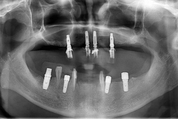

틀니, 임플란트 급여적용을 만 70세 이상으로 확대하는 내용의 국민건강보험법 시행령 개정안이 최근 국무회의를 통과했다. 이로써 개원가의 새로운 7월을 위한 제도적 준비는 모두 완료가 된 셈이다. 노인 틀니, 임플란트 급여에서 7월 1일부터 달라지는 건 딱 세가지. ▲적용 대상을 만 70세 이상으로 확대하…